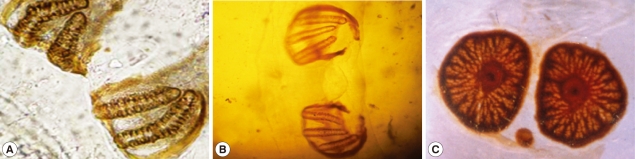

Light microscopic findings

The second stage larvae of Sarcophaga species closely resembled those of the third stage larvae with the exception of posterior spiracles.The larvae were subcylindrical in cross-sections with a flattened ventral surface, truncated posteriorly, and tapering toward the anterior extremity. The posterior end was narrowed with a pit-like depression, where the posterior spiracles are located. It ends with prominent bifid anal swellings or cerci. Body segments were banded with transverse spinous swellings. The anterior end was attenuated and had a pair of projecting papillae. Extending from the lateral surfaces of the second segment, the anterior spiracles were small and fan-like structures carrying from 7-10 branches and each branch ending with a round spiracle as shown in Fig. 2.

The posterior surface of the anal segment had a distinct cavity, and contained posterior spiracles which are a characteristic feature for differentiation as shown in Fig. 3. In the second stage larvae of Sarcophaga species, the posterior spiracles consisted of 2 elongate slits each surrounded by an incomplete sclerotized peritreme. In the third stage larvae of Sarcophaga species, the posterior spiracles are located near each other and each plat was formed of widely opened peritreme with a very indistinct button (Fig. 3A). Each plate contained of 3 elongate slits. The median one was straight, while the lateral ones were curved anteriorly (Fig. 3B). In Oestrus species, each plate of the posterior spiracles was surrounded by a complete sclerotized peritreme (Fig. 3C). Its slits were indistinct in the form of several small pores and a centrally located button.